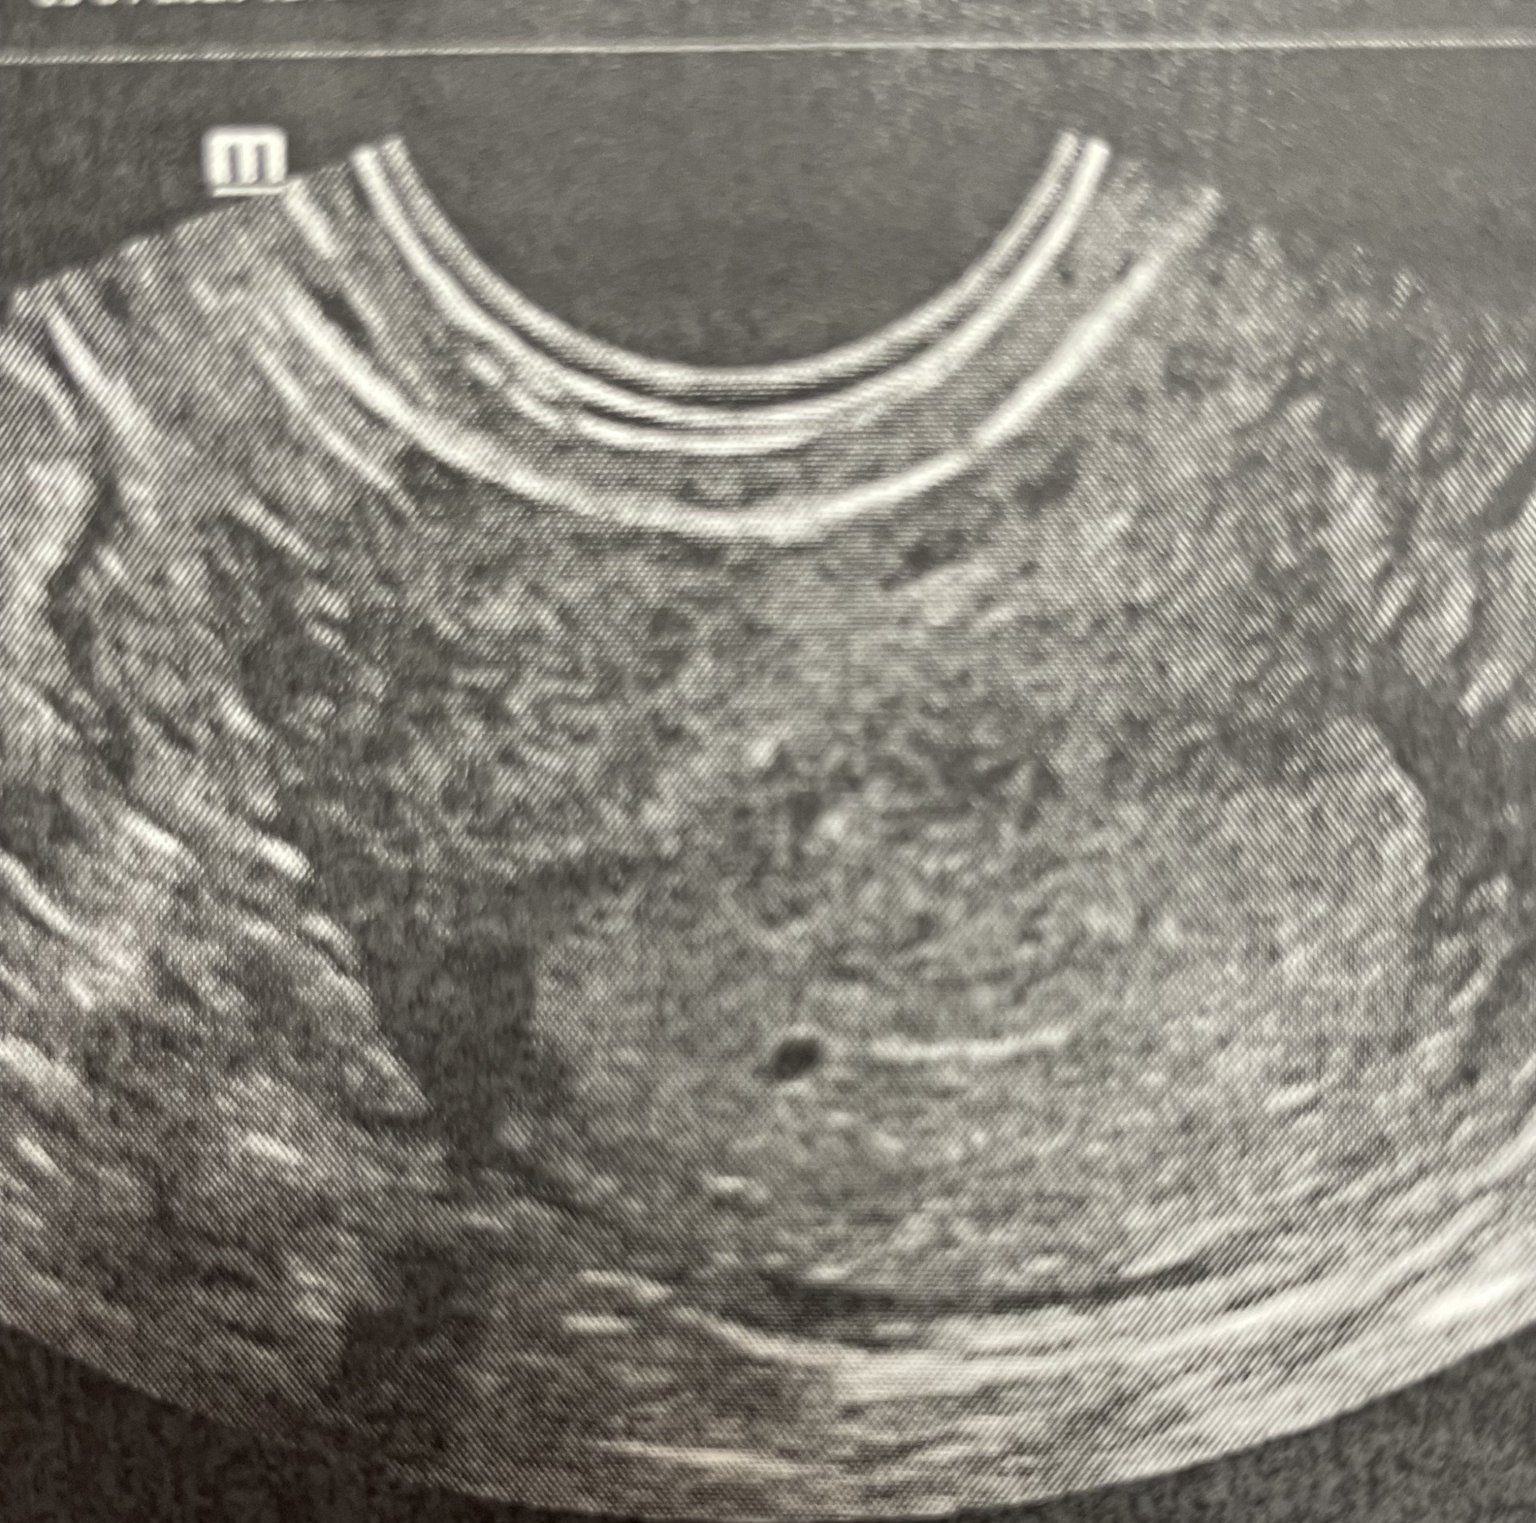

Рано е, спокойно. Предполагам по стойността, че е около 4та най-много 5 г.с. Към края на 6 г.с. се вижда вече

Това се видя днес с чхг 580 😍

При ЧХГ 580 никой не може да ви каже със сигурност, че това на снимката е плоден сак. Обикновено се визуализира стабилно чак над 1000-2000. Сега са само сенки и догадки. Не бързайте с ехографите, изчакайте малко да се вдигнат нивата, за да не се чудите после какво е видял доктора и какво не.